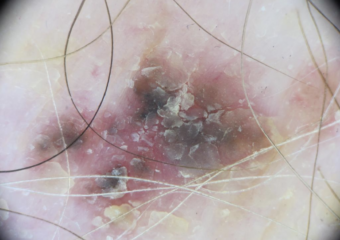

Actinic Keratosis (AK) Photos

Actinic keratosis on head or neck. Photo: International Skin Imaging Collaboration at isic-archive.com

Actinic keratosis on posterior torso. Photo: International Skin Imaging Collaboration at isic-archive.com